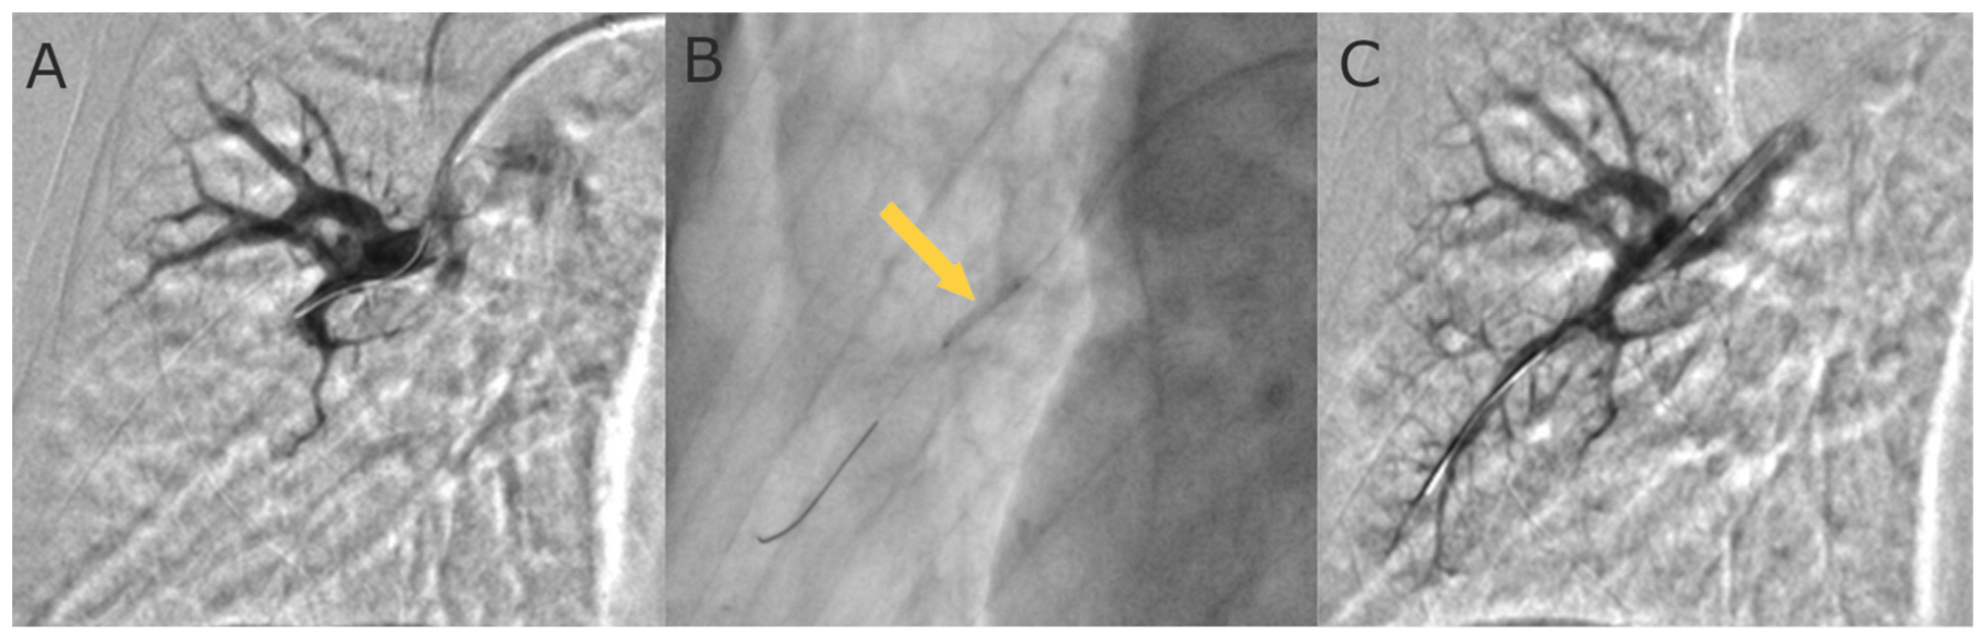

- Kawakami, T.; Ogawa, A.; Miyaji, K.; Mizoguchi, H.; Shimokawahara, H.; Naito, T.; Oka, T.; Yunoki, K.; Munemasa, M.; Matsubara, H. Novel Angiographic Classification of Each Vascular Lesion in Chronic Thromboembolic Pulmonary Hypertension Based on Selective Angiogram and Results of Balloon Pulmonary Angioplasty. Circ. Cardiovasc. Interv. 2016, 9, e003318. [Google Scholar] [CrossRef]

- Araszkiewicz, A.; Jankiewicz, S.; Łanocha, M.; Janus, M.; Mularek-Kubzdela, T.; Lesiak, M. Optical coherence tomography improves the results of balloon pulmonary angioplasty in inoperable chronic thrombo-embolic pulmonary hypertension. Postępy Kardiol. Interwencyjnej 2017, 13, 180–181. [Google Scholar] [CrossRef]